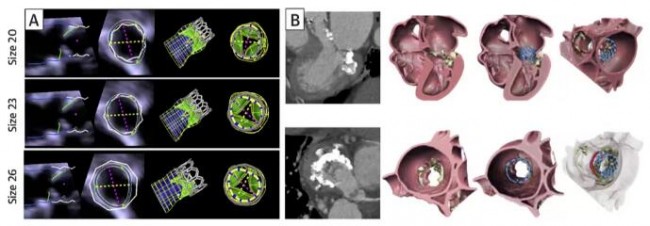

TMVR瓣膜置入后易引起左室流出道(LVOT)梗阻,可导致心律失常、充血性心力衰竭甚至死亡,特别是二尖瓣瓣膜钙化严重的老年患者,其发生率更高[12]。经食道超声及术前CTA对于LVOT梗阻的预测能力十分有限,而3D打印技术则表现出明显优势。通过加工处理获得患者特异性的3D打印模型,打印出重要解剖结构,包括二尖瓣复合体、左室流出道及心房面,通过计算机CAD模拟植入支架瓣膜假体,能动态地分析TMVR术后支架瓣膜对LVOT的影响,进一步通过调整植入假体的内径和长短,观测对LVOT的动态影响(图5)[13]。也有助于反馈给介入瓣膜的研发团队,从而不断改进和完善介入瓣膜。由于二尖瓣病变造成患者左房、左室、室间隔厚度的变化,每个患者的左室流出道及继环平面角度都不同,针对目前市面存在的介入二尖瓣,研究团队通过建立患者特异性的左心3D模型,通过将介入瓣模型植入,能更加真实地反映出患者特性的LVOT梗阻风险。

图5 二尖瓣3D打印模型模拟瓣膜植入以及LVOT梗阻风险评估

计算机建模通常可以通过有限元分析(FEA)和计算流体力学(CFD)等数值分析方法进行心脏形态和压力的量化分析,从而展示心脏血流动力学情况(图9)[19]。但计算机建模非常耗时,一般需要数小时到数天,费用较高,而且对建模简化过程中所采用简化方法和假设十分敏感。有些研究将左室心内膜假设为光滑的表面,而这种假设会导致心室内血流动力学评估出现偏差。Kulp等[20]通过对3D打印的心内膜表面补充分析肌小梁的结构,进一步完善了心室内血流的CFD模拟。结果显示,心内膜肌小梁结构对左室血流动力学有重要影响,心衰时会引起血流停滞。目前,能够用于临床的计算机建模工具(如FEA、CFD)较少,而且该技术的实施需要特殊的编程/工程技术,因此多在科研机构中使用。在临床工作中,已实现在计算机建模心脏解剖结构的基础上进行介入瓣膜的模拟植入,确定最佳瓣膜尺寸和植入深度(图10)[12,13]。在TMVR术前也可以对neo-LVOT进行评估,TMVR术后的LVOT阻塞不仅取决于neo-LVOT的解剖结构,也取决于左室血流动力学状态(图11)。